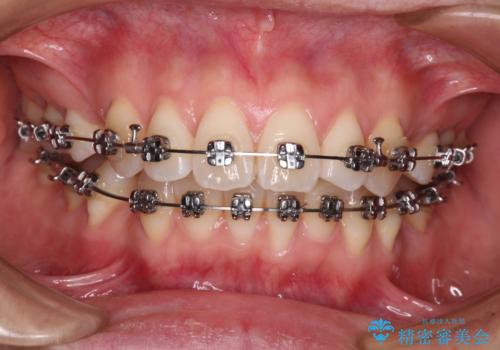

- 矯正装置

- メタルブラケット

- 治療期間

- 1年11ヶ月

非抜歯矯正ではデコボコを解消することでより口元が突出してしまうため、上下左右の小臼歯4本の抜歯を行い、ワイヤー装置による矯正治療を行うこととしました。